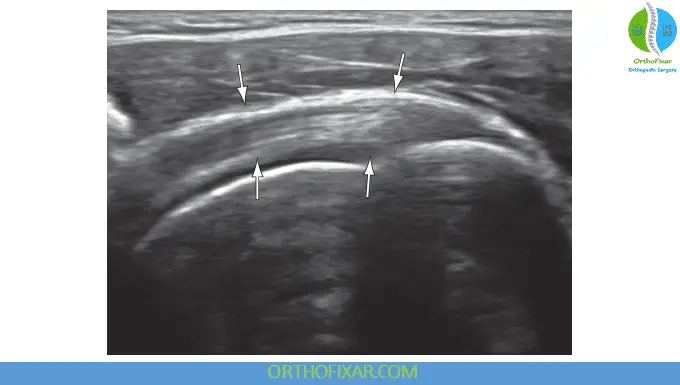

Subscapularis Tendon Ultrasound

Examination of the subscapularis tendon requires positioning the shoulder in lateral rotation. The initial transducer placement should be in long axis orientation, parallel to the tendon fibers. The tendon should demonstrate hyperechoic characteristics and can be traced laterally to its insertion on the lesser tubercle of the humerus.

Comprehensive examination requires viewing the tendon in its entirety from superior to inferior aspects, with particular emphasis placed on the superior insertion site, as this location represents the most commonly injured area in association with supraspinatus rotator cuff tears. Rotating the transducer 90 degrees allows visualization of the subscapularis tendon along its short axis. Just above the outline of the humeral head, a transverse cross-section of the subscapularis becomes visible. It is normal to observe areas of hypoechoic striations representing muscle tissue or interfaces between the several tendon bundles.